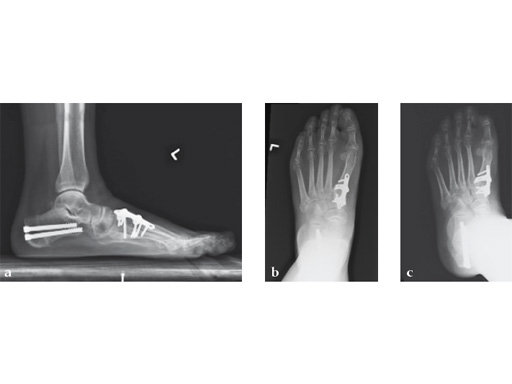

Case 4: First TMT fusion plate

A 60-year-old woman with pes plano abductovalgus (flatfoot deformity).

Case provided by Andrew Sands, New York, New York, USA

The patient was treated by headless compression screw 6.5 tuber osteotomy, TMT plantarflexing osteotomy, and first TMT fusion a plate.